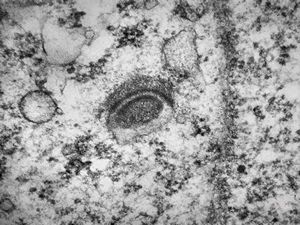

F,50y. | progressive multifocal leukoencephalopathy- viral particles in a glial cell